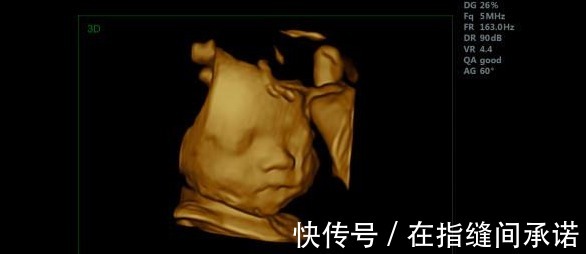

第二是记忆好孕妈可不要以为胎儿在孕妈肚子里只会吃喝睡,胎儿在孕妈肚子里的时候,就已经有了自己的记忆和想法了。细心的孕妈会发现,每次摸肚子想要跟胎宝宝互动的时候。胎宝宝都会回应孕妈妈。这是因为胎宝宝已经能够记住,妈妈摸肚子时的力度了。一般人小家伙可不管用,这就是一种记忆的表现。那胎儿又是怎么表现出自己的想法的呢?比如说孕妈生气的时候,胎儿也会不开心,这时候小家伙就会在孕妈肚子里抗议,这就是一种想法的表现。

那么知道胎儿有记忆,有想法之后,孕妈妈要抓住怀孕的黄金时期,对胎儿进行胎教。一般从怀孕六个月开始,胎儿就可以听到声音。孕妈妈可以经常给宝宝讲故事,读唐诗,听舒缓的音乐。已经有科学研究显示,胎儿在孕期听见的声音,在他们出生后,如果再次听到,在宝宝哭闹的时候,给他们放在未出生之前听过的声音,他们就会平静下来。